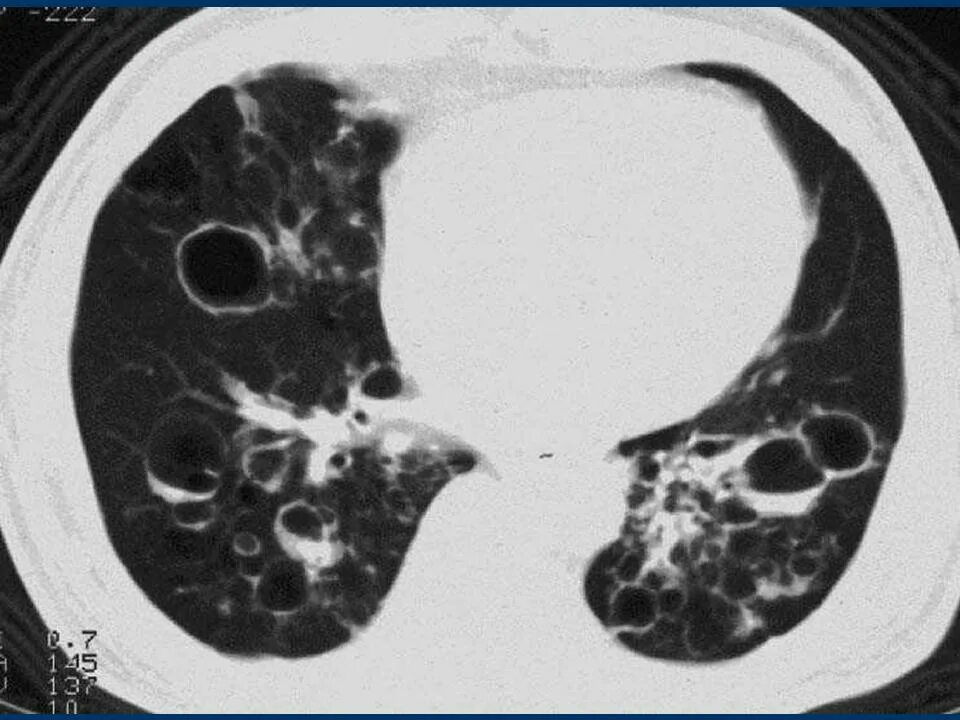

Заболевание кт